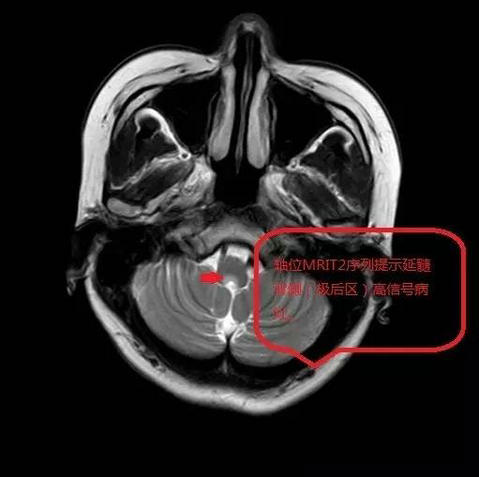

入院后,王兴萍主治医师仔细查看病情后,发现患者存在严重电解质紊乱及酸碱失衡,立即高度重视,请示何远宏主任后立即给予补液、纠正脱水、电解质紊乱、维持生命体征等抢救治疗措施,并同时完善相关检查。颅脑磁共振结果提示第四脑室前部的脑干信号异常,该区域系延髓后部。何远宏主任高度重视,立即组织全科医师讨论,经过分析病史、体征,以及查阅文献,结合患者存在顽固性呃逆、呕吐,并伴有头晕,行走不稳,言语不利等临床特点,以及延髓极后区影像异常信号,符合视神经脊髓炎谱系疾病中的极后区综合征的表现,判断该病是一种罕见的视神经脊髓炎谱系疾病,患者血液中的AQP-4抗体检查阳性对该病有特异性诊断意义。于是科室快速为患者安排了相关检查,结果显示患者血液中AQP-4抗体浓度+++(1:320),脑脊液AQP-4抗体浓度+(1:1),支持诊断“极后区综合症”。该病是一种罕见疾病,目前还尚未被大家所认识。郑州大学五附院神经内科一病区结合丰富的经验,扎实的神经内科知识,并查阅相关医学文献,准确及时的诊断了该病。明确诊断后,立即给予甲强龙激素冲击并联合丙种免疫球蛋白治疗,患者的顽固性呃逆完全消失了,未再出现恶心、呕吐症状,也能进食了,行走不稳也得到了控制,将于近期出院。